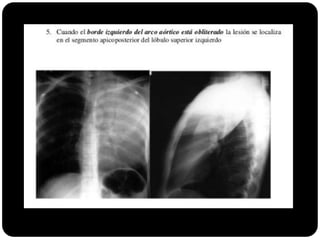

E agora?

 Se borrar arco aórtico qual o segmento

afetado?

 Apico posterior (LSE)